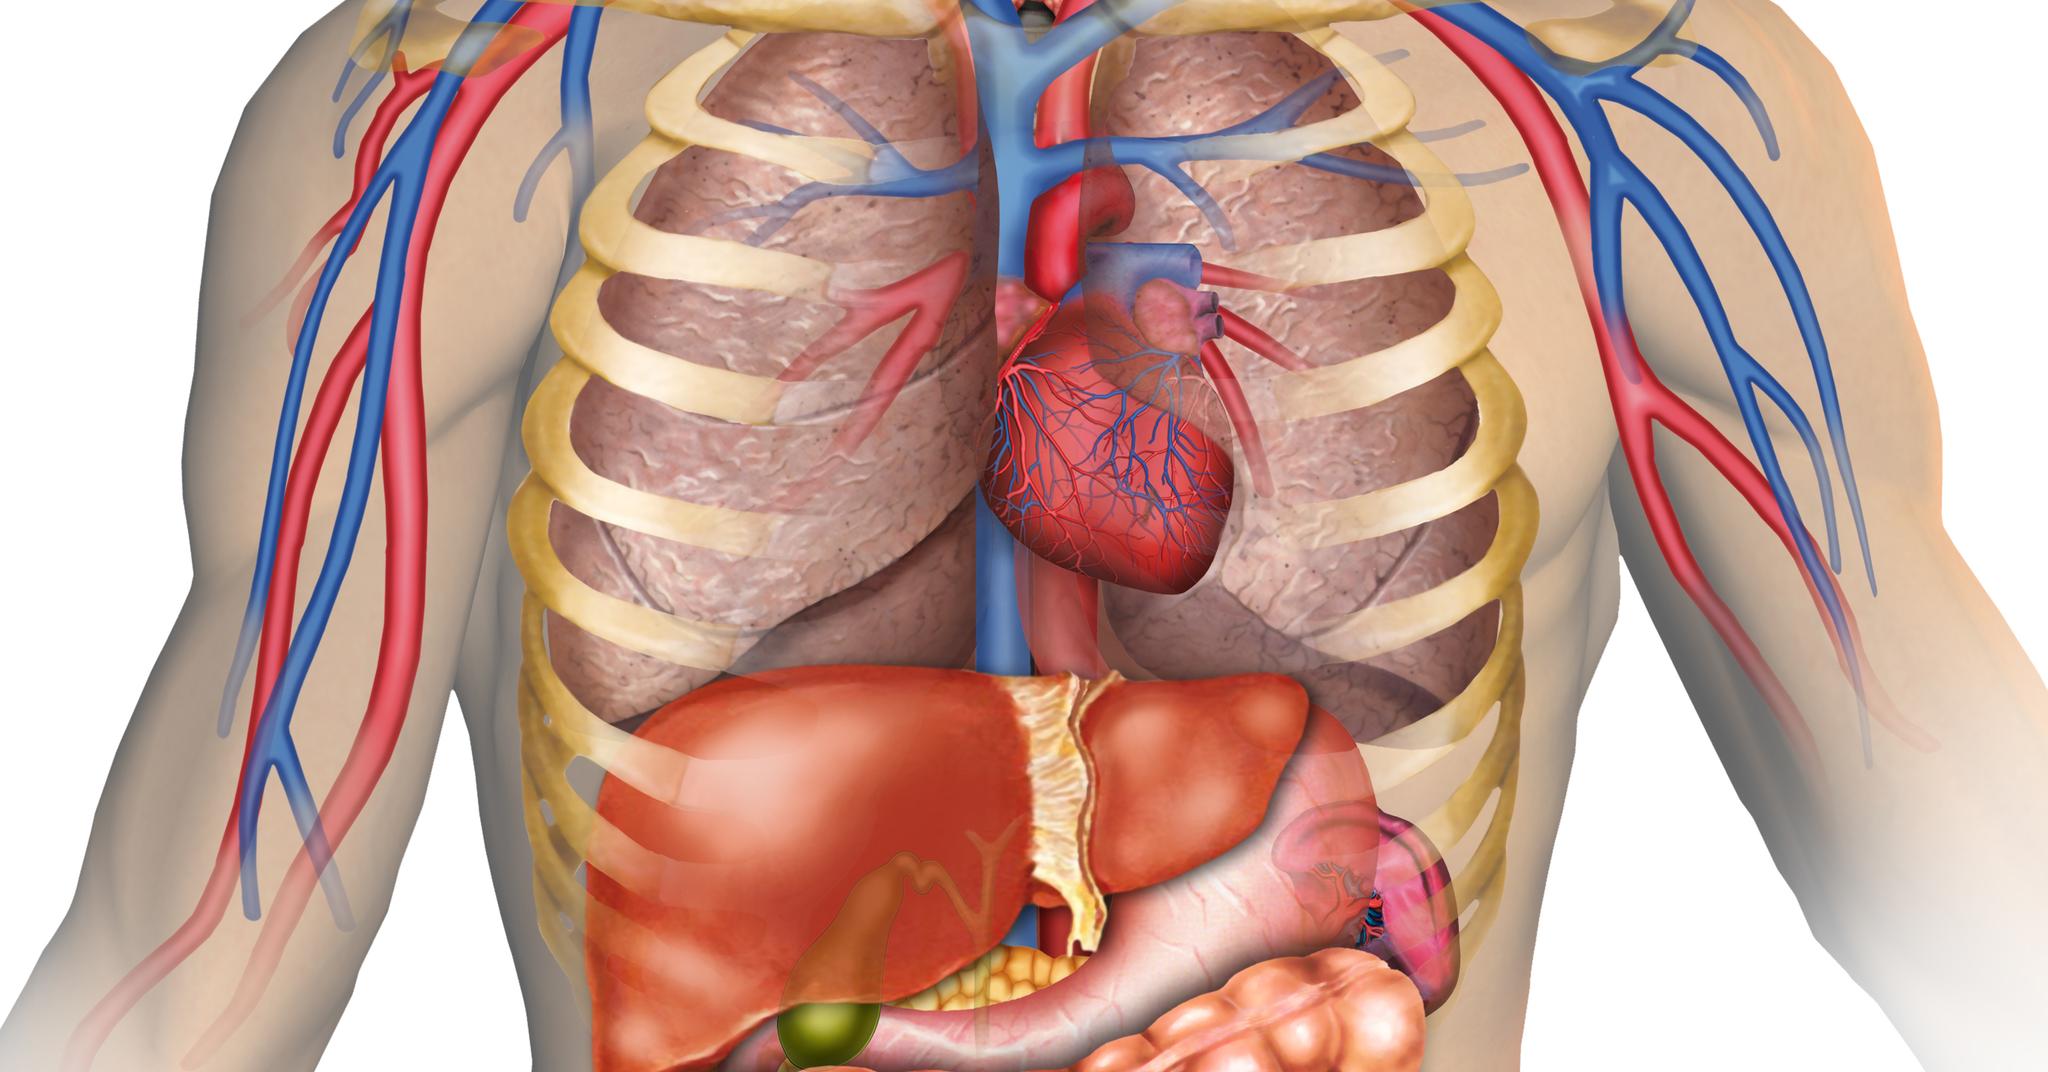

Сердце у человека располагается в грудной полости.

Сердце в грудной клетке расположено.

Где расположено сердце у человека анатомия.